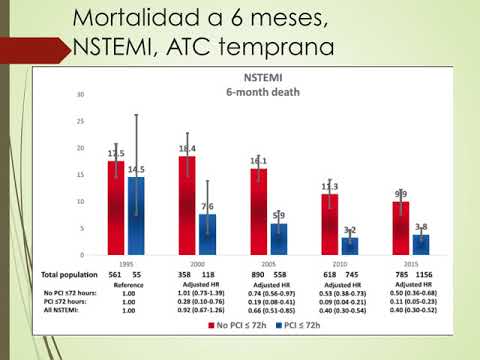

Evaluación y tratamiento invasivo temprano vs. estándar en pacientes con SCASEST. Dra. Florencia Cichello. Residencia de cardiologia. Hospital C. Argerich. Buenos Aires